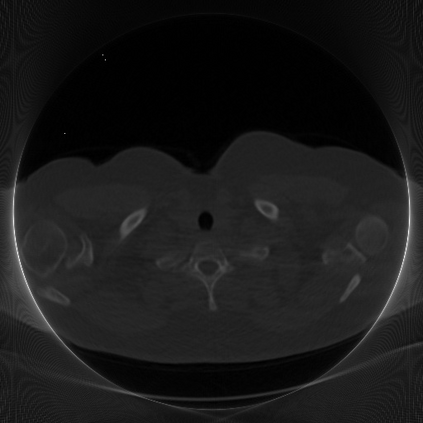

Low-Dose Computed Tomography (LDCT) technique, which reduces the radiation harm to human bodies, is now attracting increasing interest in the medical imaging field. As the image quality is degraded by low dose radiation, LDCT exams require specialized reconstruction methods or denoising algorithms. However, most of the recent effective methods overlook the inner-structure of the original projection data (sinogram) which limits their denoising ability. The inner-structure of the sinogram represents special characteristics of the data in the sinogram domain. By maintaining this structure while denoising, the noise can be obviously restrained. Therefore, we propose an LDCT denoising network namely Sinogram Inner-Structure Transformer (SIST) to reduce the noise by utilizing the inner-structure in the sinogram domain. Specifically, we study the CT imaging mechanism and statistical characteristics of sinogram to design the sinogram inner-structure loss including the global and local inner-structure for restoring high-quality CT images. Besides, we propose a sinogram transformer module to better extract sinogram features. The transformer architecture using a self-attention mechanism can exploit interrelations between projections of different view angles, which achieves an outstanding performance in sinogram denoising. Furthermore, in order to improve the performance in the image domain, we propose the image reconstruction module to complementarily denoise both in the sinogram and image domain.